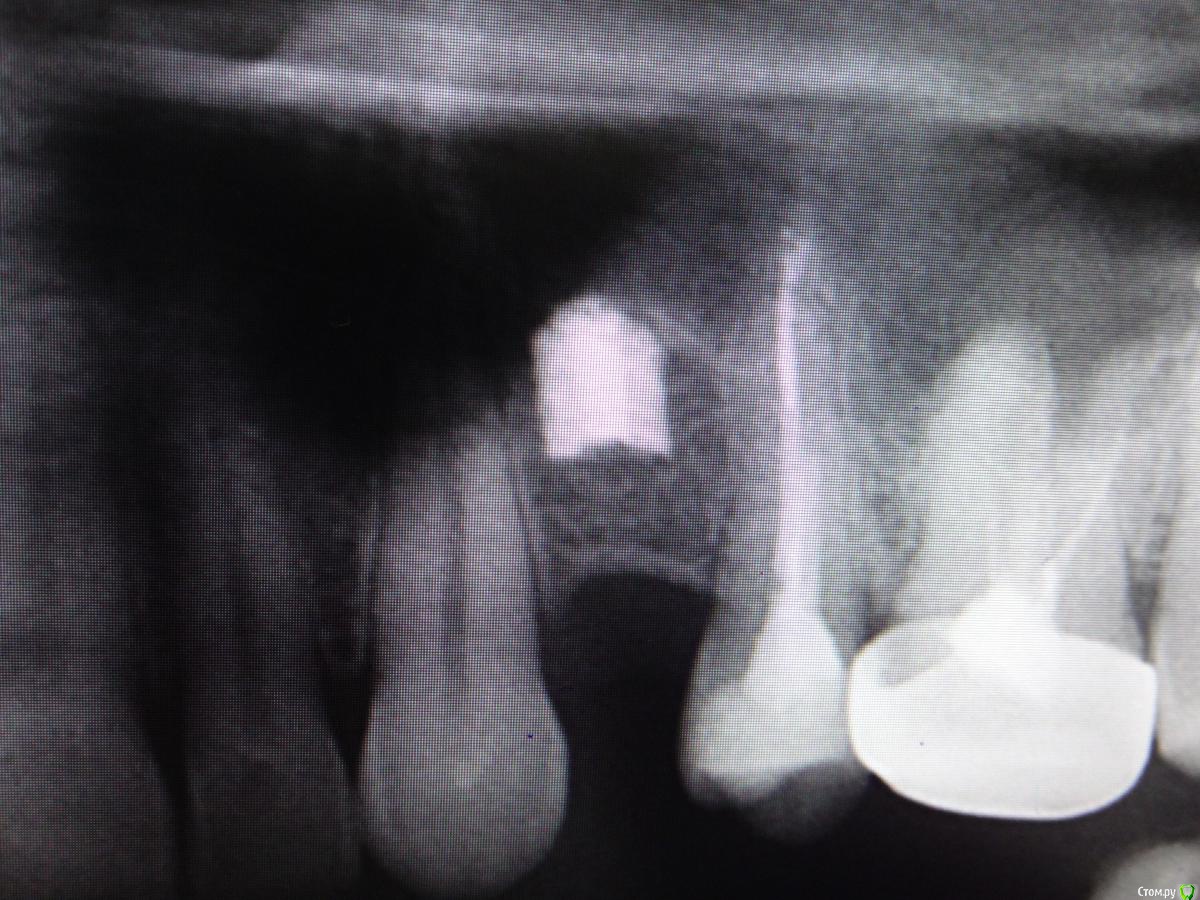

Slaggy Опубликовано 24 января, 2015 Поделиться Опубликовано 24 января, 2015 Господа, что за система имплантов, кто торгует запчастями?Раскрутилсо. Знакомая. Просит восстановить зуппчик наместо. Ссылка на комментарий

Kurz1981 Опубликовано 28 января, 2015 Поделиться Опубликовано 28 января, 2015 (изменено) Господа, что за система имплантов, кто торгует запчастями?DSC01829.JPGDSC01830.JPGDSC01831.JPGРаскрутилсо. Знакомая. Просит восстановить зуппчик наместо.Очень сильно похоже на кейстоун http://whatimplantisthat.com/wp-content/uploads/2012/03/Restore-TPS-Coated.jpg Что то больше похожего судя по вашему рентгену я не нашел. Изменено 28 января, 2015 пользователем Kurz1981 Ссылка на комментарий

Slaggy Опубликовано 28 января, 2015 Поделиться Опубликовано 28 января, 2015 Возможно наши - Томск, Екатеринбург.Пациент сказал сегодня.Пойду порою яндыкс. Ссылка на комментарий

Slaggy Опубликовано 21 февраля, 2015 Поделиться Опубликовано 21 февраля, 2015 Господа, что за система имплантов, кто торгует запчастями?DSC01829.JPGDSC01830.JPGDSC01831.JPGРаскрутилсо. Знакомая. Просит восстановить зуппчик наместо. Оказались Новокузнецкими старыми. Ссылка на комментарий